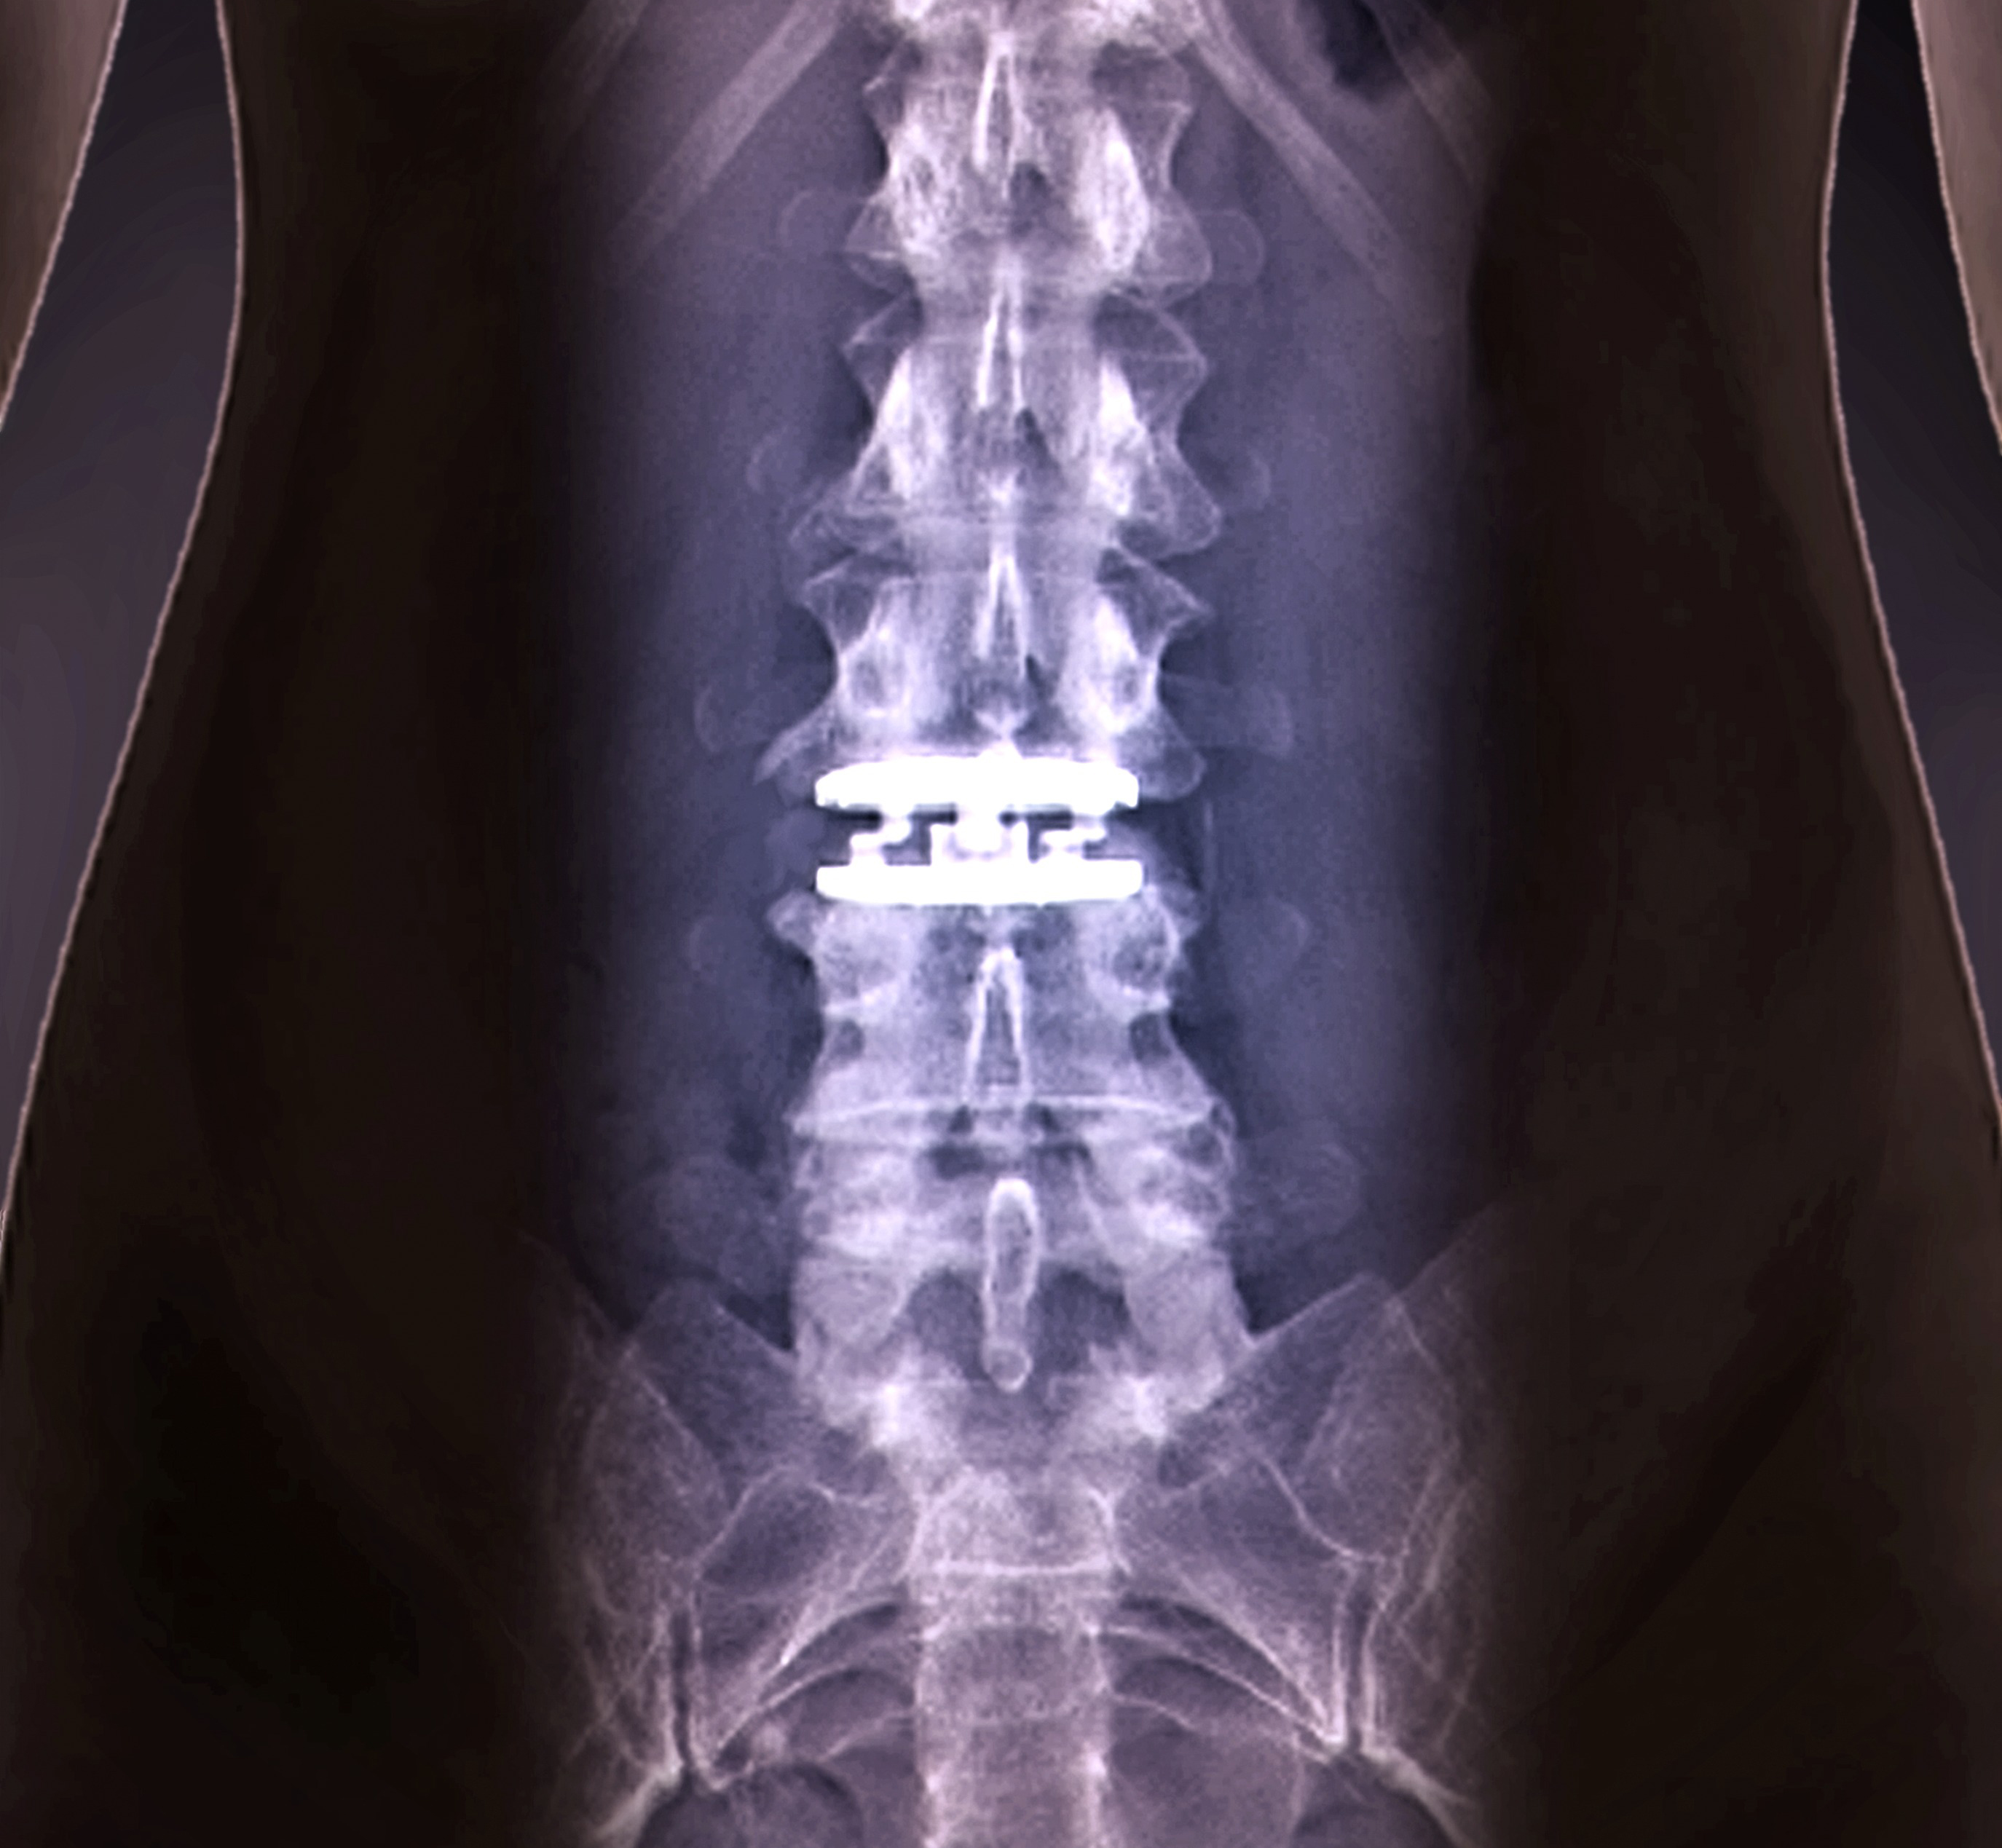

인공디스크치환술

척추신경을 누르는

디스크 마디 전체를 모두 제거하고 인체디스크와 유사한 탄력성을 지닌 인공 디스크로 바꿔주는 것

입니다.

척추신경을 누르는 디스크 마디 전체를 모두 제거하고 양쪽의 티타늄 금속판 가운데에 폴리우레탄 핵으로 구성된 인공디스크로 바꿔줍니다.

인공디스크 수술이 효과적인 환자

디스크 변성증으로 디스크의 기능이 소실된 환자

퇴행성 디스크 질환으로 만성 통증이 있는 환자

척추변형이나 척추가 흔들리는 척추 불안정증이 동반되는 환자

퇴행현상으로 디스크 간격이 좁아져 신경을 압박하는 환자

오랜기간 보존적 치료를 시행해도 효과가 없는 디스크 환자

참기 어려운 동통·신경약화·대소변 기능의 장애 등으로 일상생활이 어려운 환자

수술특징

수명이 영구적이다.

재발의 위험이 거의 없다.

최소절개로 회복 및 일상복귀가 빠르다.

고유의 운동성을 유지하여 움직임과 활동에 재약을 받지 않는다.